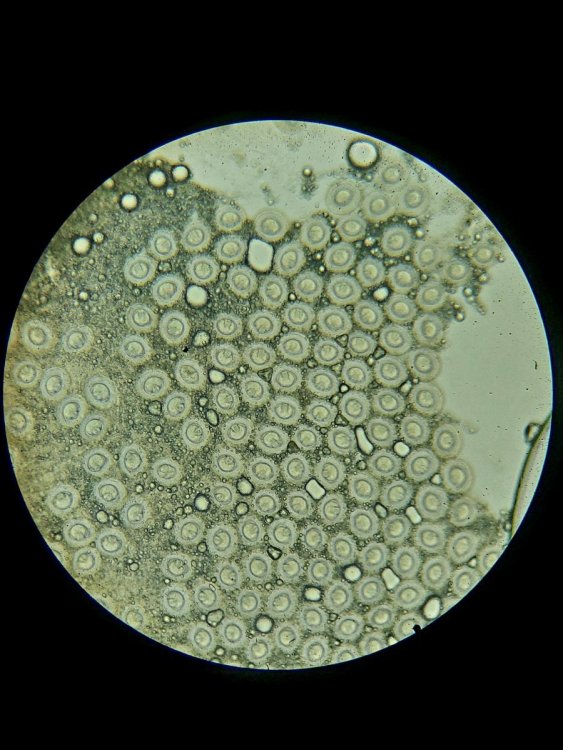

1. Фото крахмал (кружочки) - голубь